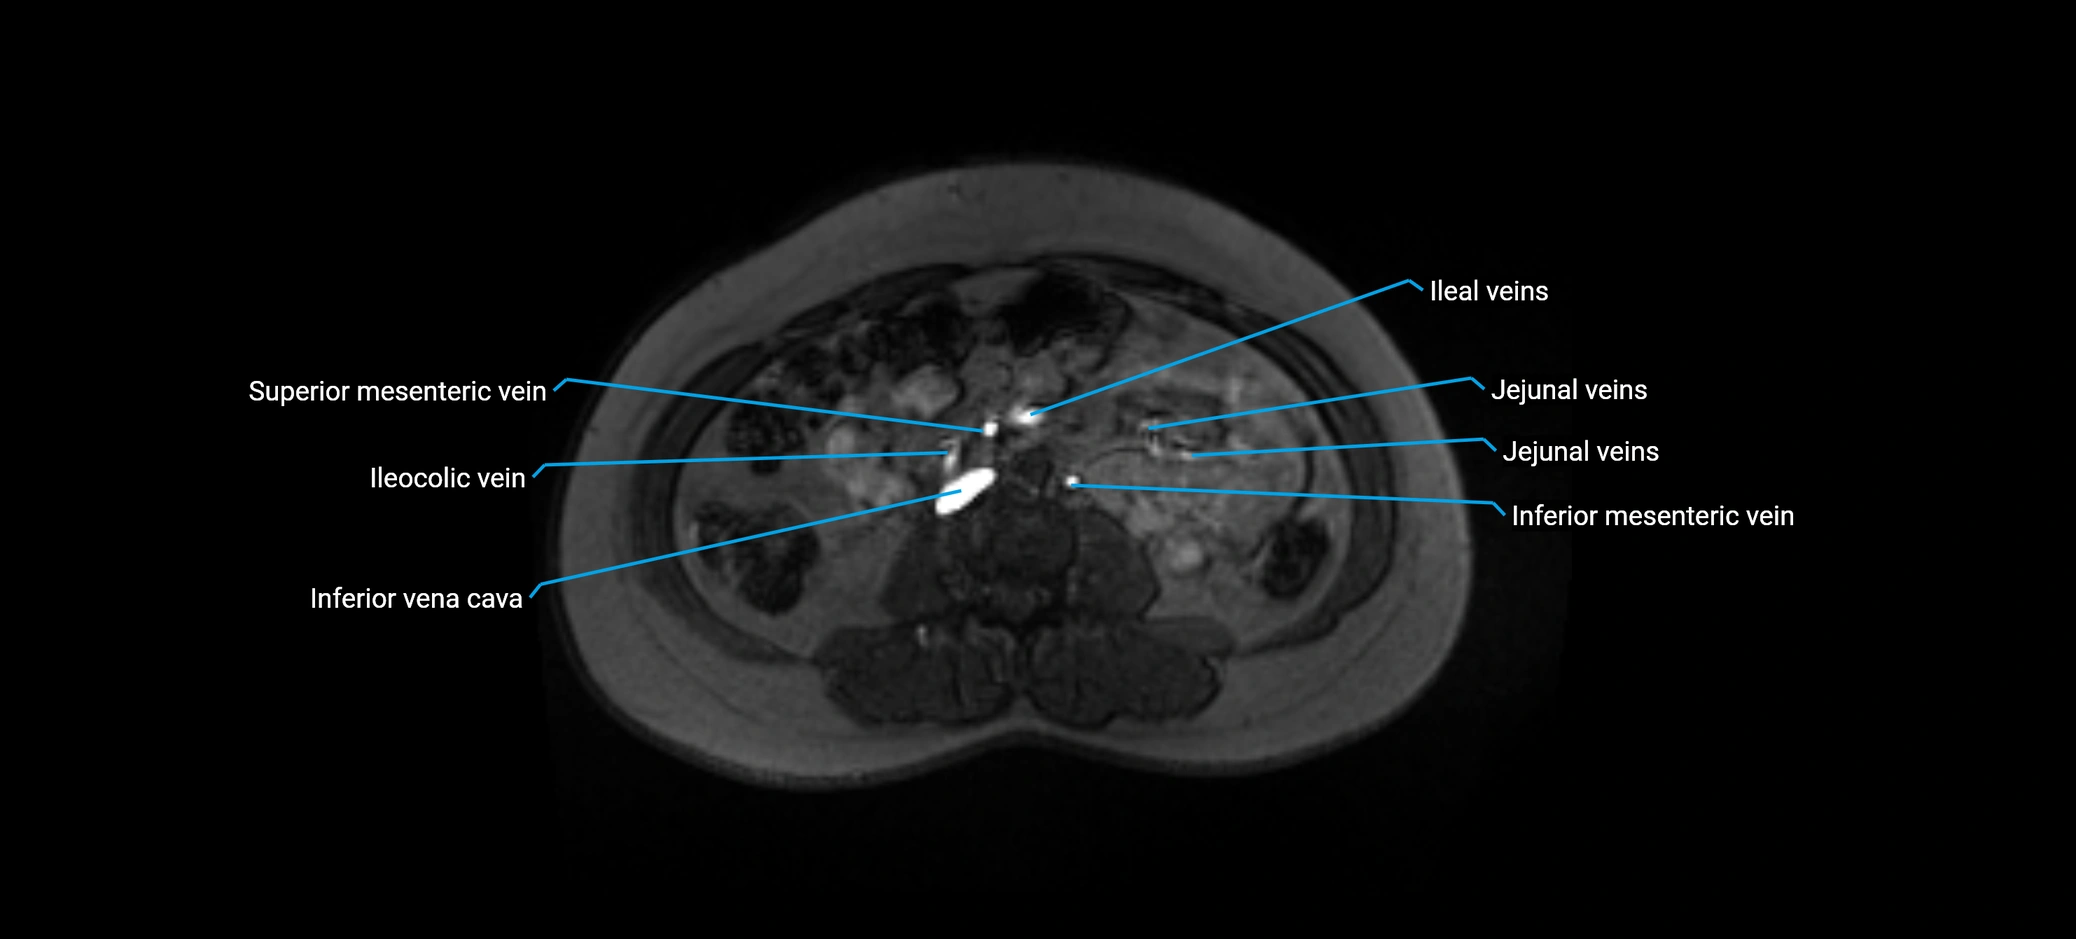

MRI image

image